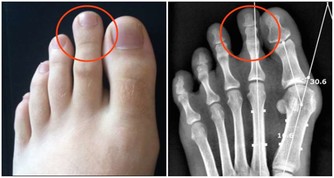

5. 你罹患某些癌症的風險更高

你可能正在想盡一切辦法預防癌症,那麼,讓硒保持最佳水平吧。

因為,它可以讓胃癌、膀胱癌和前列腺癌的風險降低31%,反之則會增加其風險。